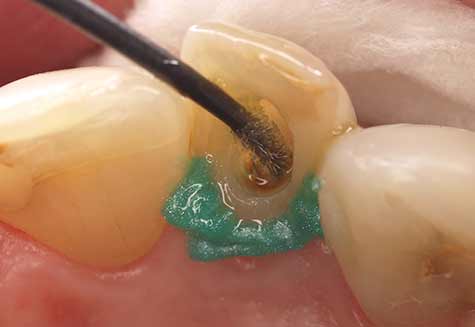

Het gebruik van Futurabond U in de Self-Etch-techniek is zinvol in klinische casussen waarbij alleen de dentinesubstantie hoeft te worden geëtst en/of het glazuurgebied geen intensieve en zeer agressieve conditionering nodig heeft. Aan de hand van de klinische casus van een 42-jarige patiënt worden de bevestiging van een stift en het gebruik van Futurabond U na een zeer ruime caviteitpreparatie voor een prothetische restauratie getoond, waarbij grotendeels alleen dentine werd geëtst. Door speciale applicators (Endo Tim, VOCO) voor gebruik in het wortelkanaal kan het adhesief ook daar zijn volledige werking ontwikkelen, omdat een volledige bevochtiging van de kanaalwanden plaatsvindt. Het actief inmasseren van Futurabond U in alle dentine-oppervlakken in het wortelkanaal bereidt de tandstructuur optimaal voor de aansluitende bevestiging voor (afb. 4-6). Een in het wortelkanaal lastig uit te voeren uitharding met licht is bij het duaalhardende Futurabond U niet nodig.

Afb. 5: Met de speciale applicator EndoTim (VOCO) wordt het wortelkanaal betrouwbaar bevochtigd met Futurabond U

Afb. 6: Applicatie van het opbouw- en bevestigingsmateriaal Rebilda DC (VOCO)